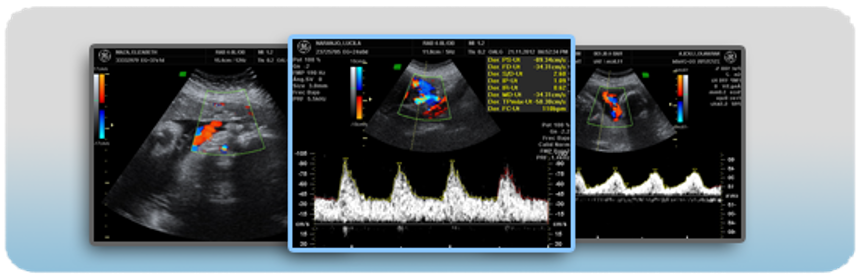

28 febrero, 2022Doppler Obstétrico Feto-Placentario

Evalúa en forma no invasiva el flujo de los vasos sanguíneos de la placenta, del feto, útero y del cordón umbilical, determina cómo está el flujo de sangre que le llega al feto, y por lo tanto el oxígeno y los nutrientes que recibe el bebé a través de la placenta. Si hay algún cambio en el flujo sanguíneo nos permitirá saber si hay necesidad de anticipar el parto. El uso del doppler reduce el número de muertes perinatales e intervenciones obstétricas innecesarias.

Este estudio nos permite predecir el riesgo que tiene la embarazada de presentar enfermedades como la preclamsia o restricción del crecimiento intrauterino en el feto, así como su seguimiento clínico.